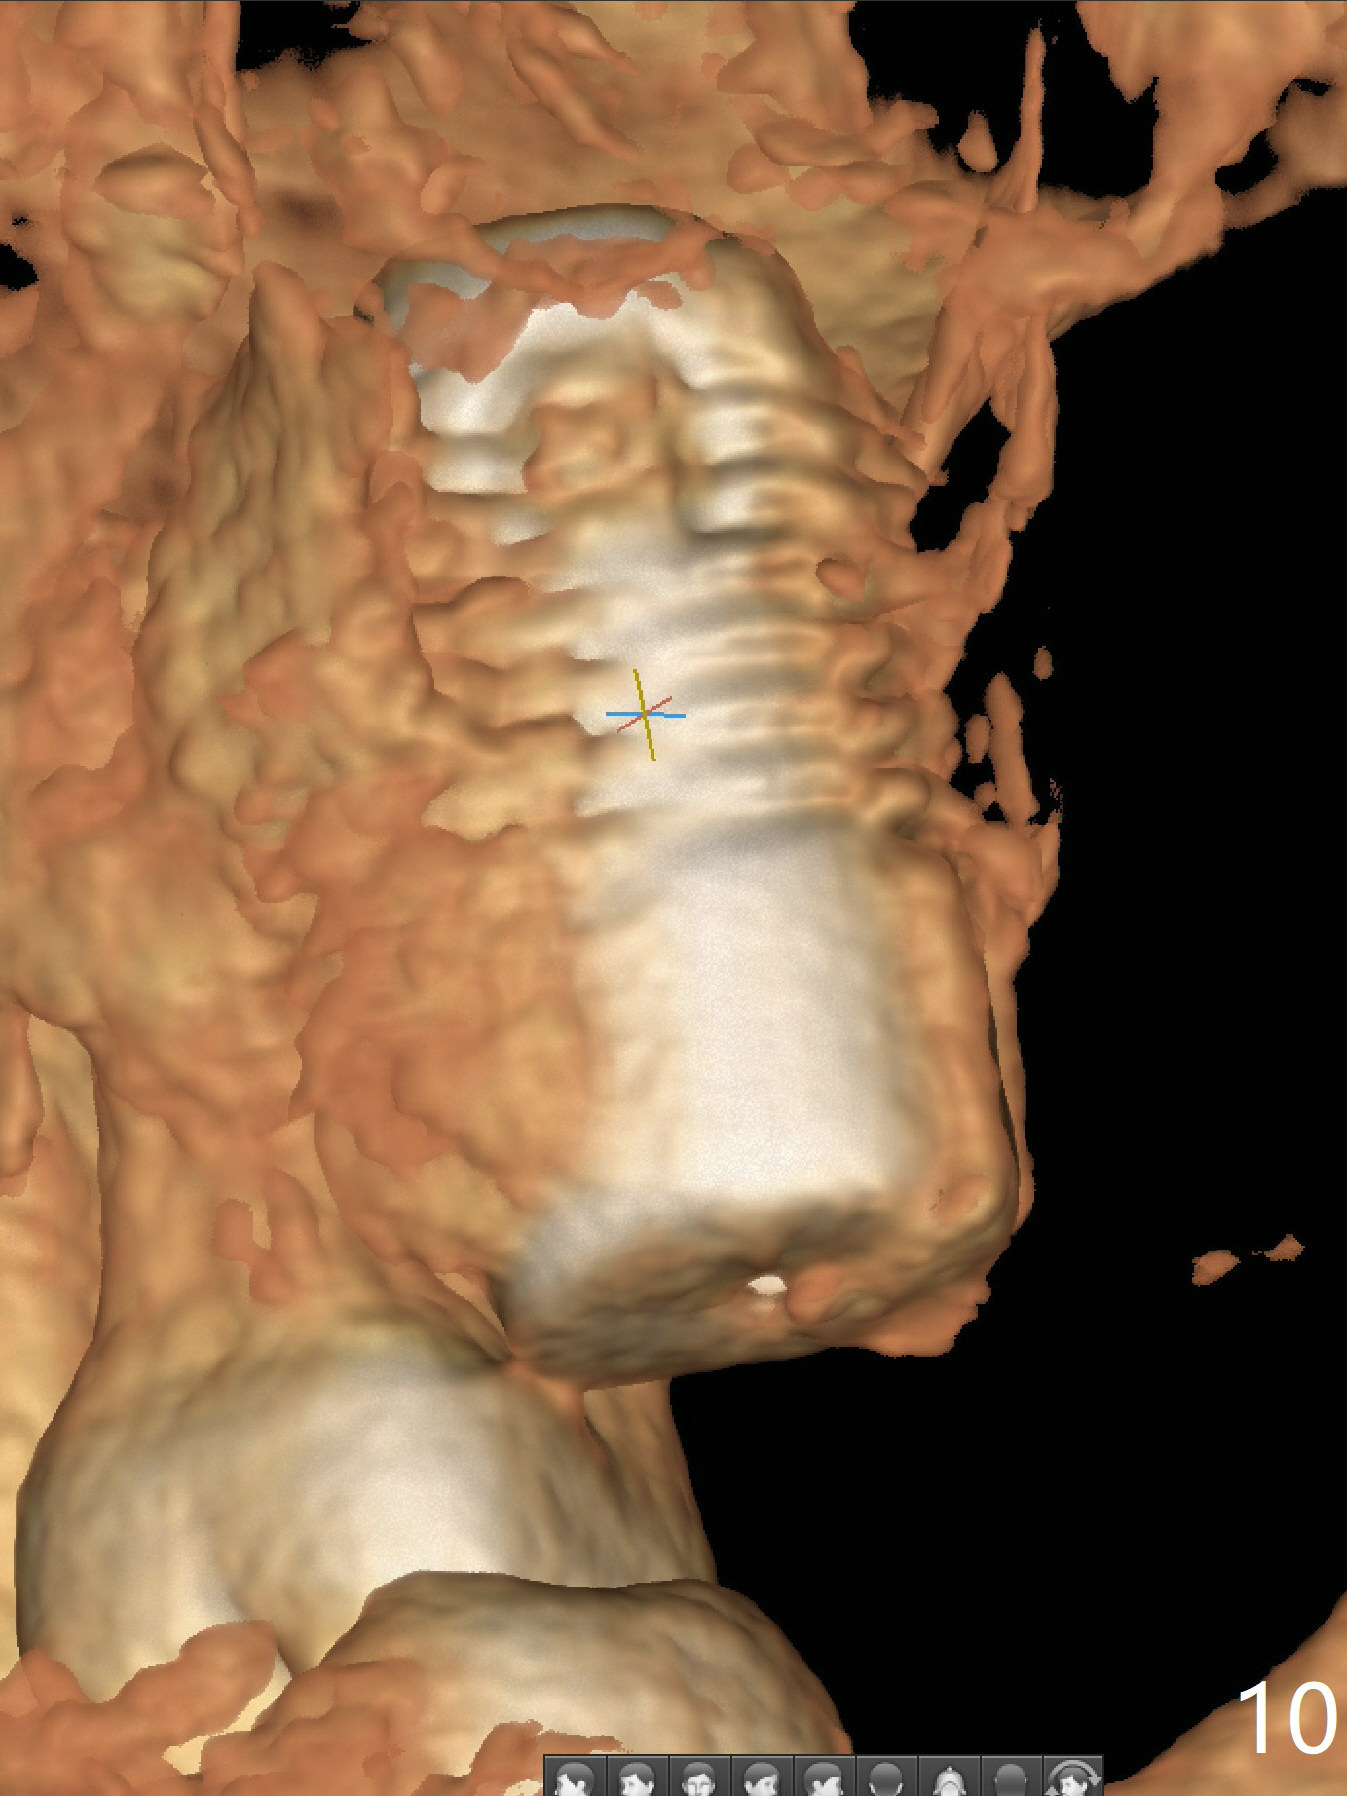

Preop exam shows that the tooth #2 has split into the buccal (Fig.1 B) and palatal (P) halves. When the tooth is extracted (Fig.2), there is a large piece of granulation tissue between these halves. The socket is large with sinus floor having pointed perforation. The latter is enlarged with rounded tapered Tatum osteotomy 2-4 mm, followed by tapered and then rounded taps. A 6.8x14 mm rounded tap has barely enough stability (Fig.3). Following placement of 2 PRF plug and 2 PRF membranes and allograft/Osteogen, a 8x17 mm cylindrical implant is placed with 60 Ncm (implant machine reading), however the implant is unstable (Fig.4). More graft is placed around the implant. With placement of 6x3 mm abutment, an immediate provisional is fabricated to close the socket. There is nasal discharge for a few days postop. PAs taken nearly 6 months postop show no bone loss (Fig.5,6). The definitive crown is cemented with access hole; there is no residual cement (Fig.7 (9 months postop)). The crown is loose 1 month post cementation (last March, Fig.8 with periimplant space (*)). The unipost was not cemented due to gag reflex. He refuses treatment immediately because of the allergy season. When he returns, spray a topical to his throat. Following crown removal, implant is found to have mobility. Panoramic X-ray (Fig.9) and CT (Fig.10,11) show fibrointegration (space) and implant intrusion into the sinus (S) without bone formation. After implant removal, the sinus floor and membrane are found to have been perforated. Osteogen plug is placed, followed by Vanilla/Osteogen (Fig.12 *) and Osteogen plug. It appears that an immediate implant is contraindicated when there is severe infection (Fig.2) with sinus floor perforation. In this case, the bone density at the upper 2nd molar is low (Fig.10 distopalatal view of 3-D image). Bone expansion and condensation is needed for implantation. Progressive loading is also necessity prior to impression.